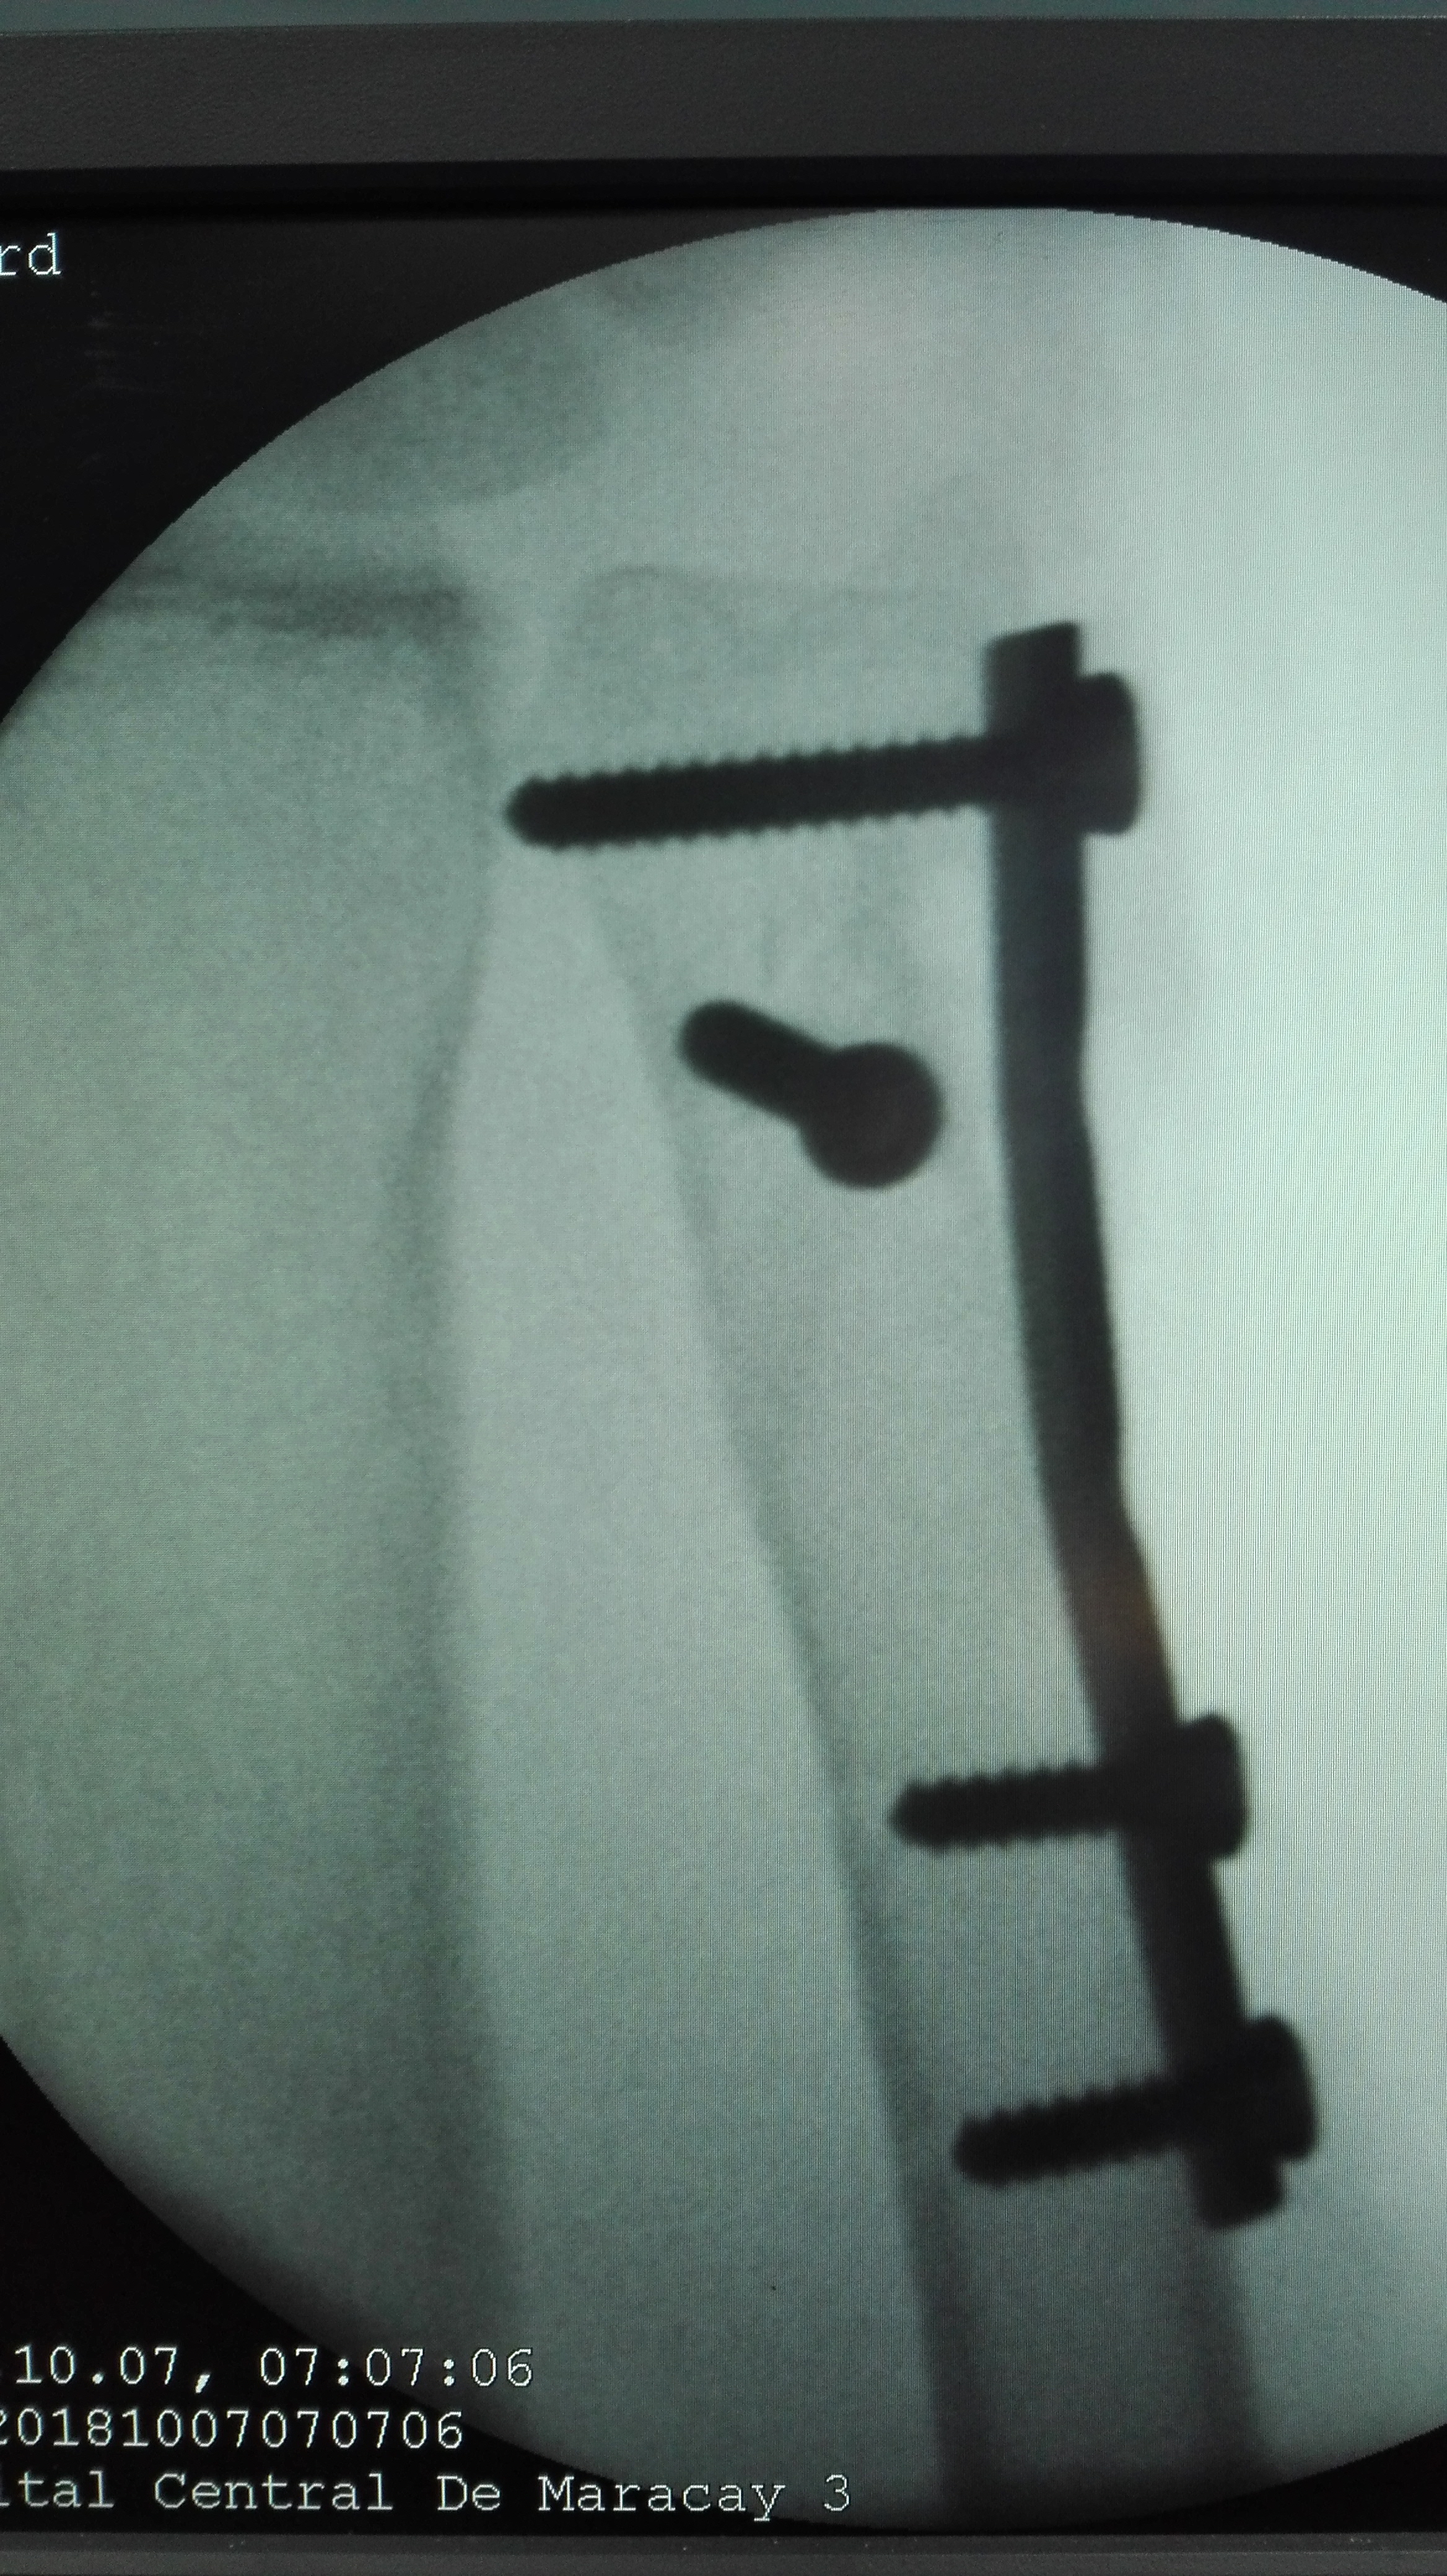

Recently we had the opportunity to have surgery for a fracture of the ulna, they are not very frequent in isolation as most of the time they present together with fractures of the radius. The osteosynthesis of these fractures may seem easy but any error can make it difficult for patients to perform their manual tasks in the same way as before. Today we will talk about: The Cubitus.

stable:

when the displacement of bone fragments does not reach 30%. Also in this category is the so-called fracture of the green stem, in which the cortex and the periosteum between the bones are not damaged (these are necessary to block rotation);unstable:

when the displacement of bone fragments does exceed 30% or form an angle greater than 10 degrees. Another possibility is a fracture that affects the cortex between the bones. In this case there may be other injuries that accompany the picture, such as dislocation of the elbow and fracture of the radius.